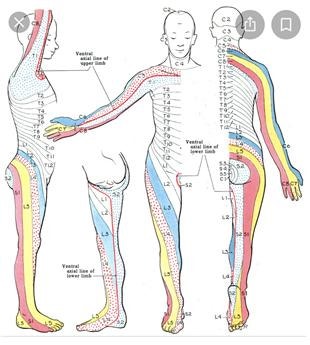

- heavy, dull pain around the neck and upper trapezius

- tension-type headaches when symptoms are more severe

- persistent neck pain and muscle tension

- increased activity in superficial neck muscles (e.g., upper trapezius)

- headaches originating from the neck region